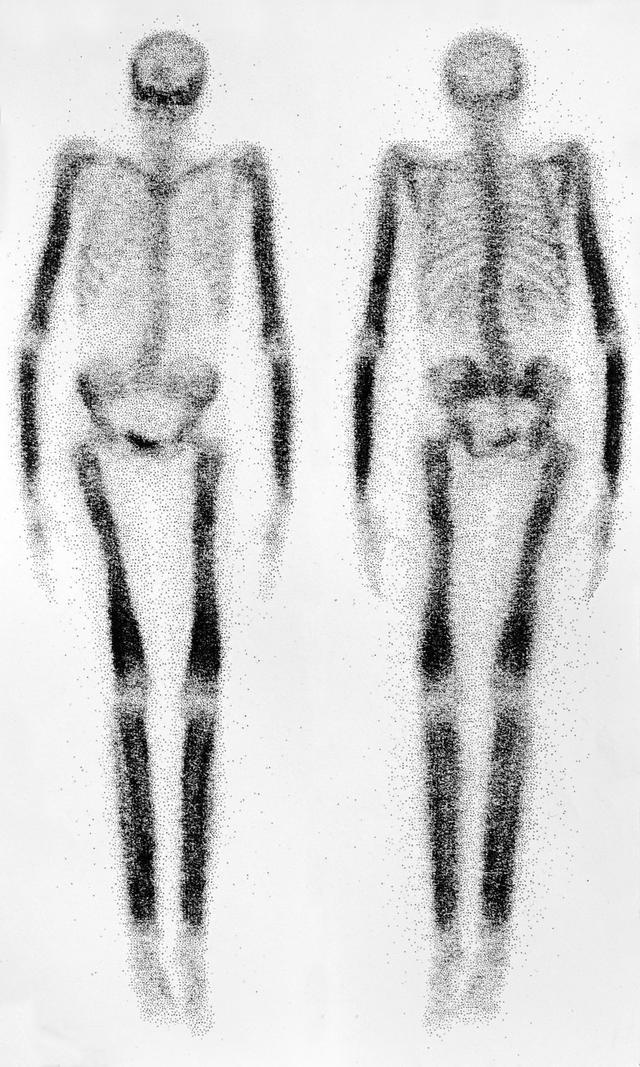

全身骨显像

骨显像主要是为了检查是否有肺癌的骨转移,对于骨转移也是需要采取单独治疗的,比如局部的放疗以及唑来膦酸治疗。